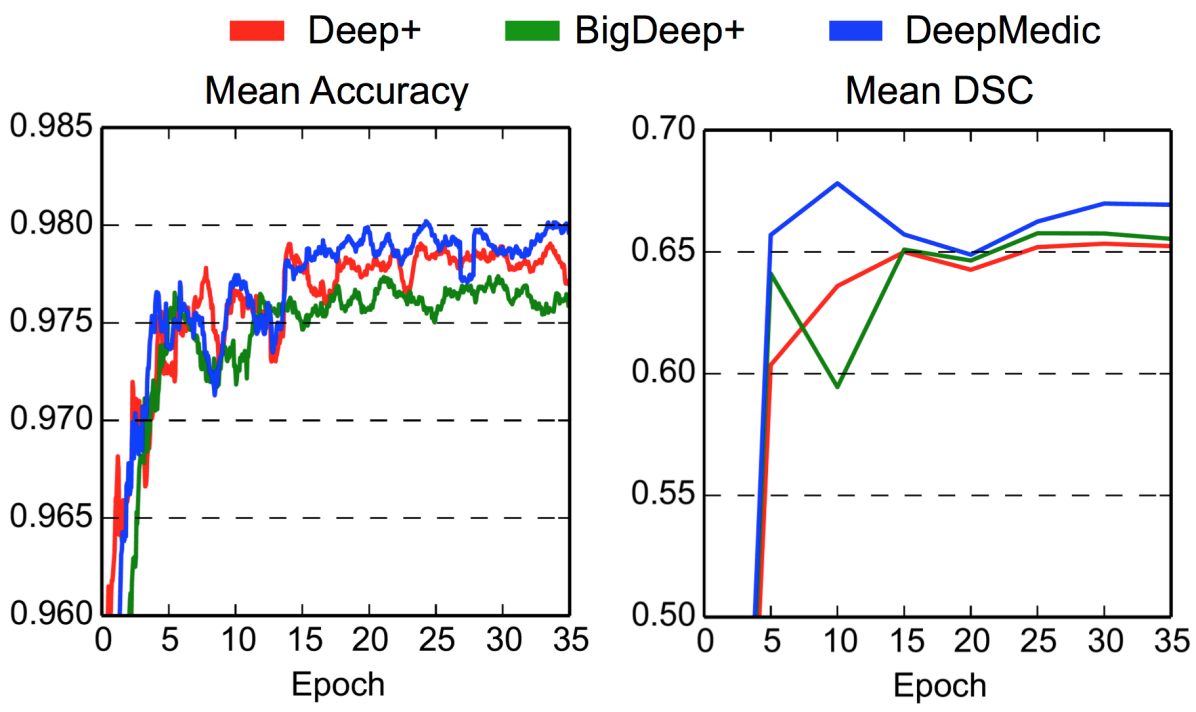

The final version of the proposed network architecture, referred to as “DeepMedic”, is built by extending the Deep+ model with a second convolutional pathway that is identical to the first one. Two hidden layers are added for combining the multi-scale features before the classification layer, resulting in a deep network of 11-layers (cf. Fig. 5). The input segments to the second pathway are extracted from the images down-sampled by a factor of three. Thus, the network is capable of capturing context in a area of the original image through the receptive field of the lower-resolution pathway, while only doubling the computational and memory requirements over the single pathway CNN. In comparison, the most recent 2D CNN systems proposed for lesion segmentation (Havaei et al. (2015); Pereira et al. (2015)) have a receptive field limited to voxels.

Figure 8 shows the improvement DeepMedic achieves over the single pathway model Deep+. In Fig. 9 we show two representative visual examples of this improvement when using the multi-scale CNN. Finally, we confirm that the performance increase can be accounted to the additional context and not the additional capacity of DeepMedic. To this end, we build a big single-scale model by doubling the FMs at each of the 9-layers of Deep+ and adding two hidden layers. This 11-layers deep and wide model, referred to as “BigDeep+”, has the same number of parameters as DeepMedic. The performance of the model is not improved, while showing signs of over-fitting.